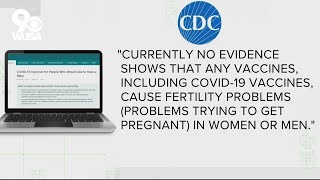

VERIFY: No link between coronavirus vaccines and fertility

VERIFY: No link between coronavirus vaccines and fertility No link between coronavirus vaccines and fertility

No link between coronavirus vaccines and fertility Verify: No link between vaccines, infertility

Study finds no link between infertility and COVID vaccination VERIFY: No, there’s no evidence that COVID-19 vaccines cause infertility in women or men

VERIFY: No, there’s no evidence that COVID-19 vaccines cause infertility in women or men VERIFY: No evidence that COVID-19 vaccine will lead to infertility or sterilization